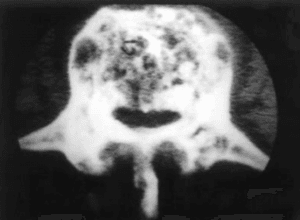

En la columna las vertebral sufren una deformación con agrandamiento, endurecimiento y redondeamiento de sus bordes, con estructura ósea desordenada.

En los métodos de diagnóstico por imágenes se puede evidenciar las deformidades, la pérdida de densidad ósea así como la esclerosis y las fractura patológicas, se destacan la radiografía y la tomografía computada.

El remodelado del hueso de la vértebra se expresa en una expansión del hueso en todas las direcciones, llevando a osteoartropatía de faceta con hipertrofia y una reducción del canal con estenosis espinal.